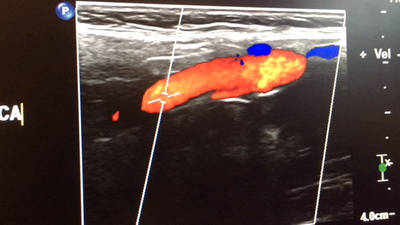

Дело в том, что в Израиле у врачей есть потребность и желание подрабатывать частной практикой (пусть и не такая жуткая, как в России). Поэтому, например, в одной из популярных частных клиник «Тель-Авив Медикал Центр» ведут приём врачи из медицинской элиты Израиля. Даже израильтянам нелегко попасть к ним на прием, в государственной клинике. Скажем, есть известный врач — кардиолог, специалист по неинвазивной кардиологии - профессор Миха Файнберг. Он руководит отделением в «Шибе», это большая государственная клиника. Но к нему там попадают на УЗИ сердца в редких случаях — когда простым, не «звёздным», врачам трудно поставить диагноз. Просто из очереди к нему никто и никогда на приём не зайдёт. А в «Тель Авив Медикал Центр» он принимает и диагностирует без предварительного фильтра. Кстати, и работает он здесь на ультразвуковом оборудовании последнего поколения, что не всегда происходит в государственных больницах.